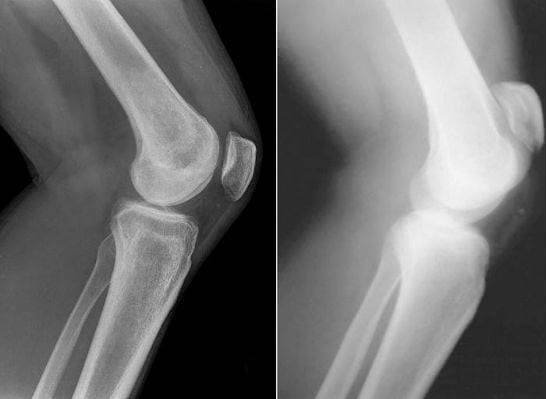

De exemplu, vă puteți uita la fotografiile realizate în spitale:

1. Articulația genunchiului unui pacient cu artroză (pacientul a folosit metodele "clasice" de tratament). Preparatele injectabile îi ușurau durerea pentru un timp scurt, dar nici întru-un caz nu au încetinit progresia bolii. Ca urmare, trebuia să-și ampută piciorul. Acum este persoană cu dizabilități.

Acestea sunt imagini ale articulațiilor "înainte" și "după" utilizarea HondroLife.